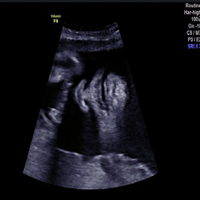

Ultrasound is a painless and safe procedure which uses sound waves to obtain a medical image or picture of various organs and tissues in the body.

Ultrasound produces very precise images of your soft tissues (heart, blood vessels, uterus, bladder, etc.) and reveals internal motion such as heart beat and blood flow. It can detect diseased or damaged tissues, locate abnormal growths and identify a wide variety of changing conditions, which enable your doctor to make a quick and accurate diagnosis.